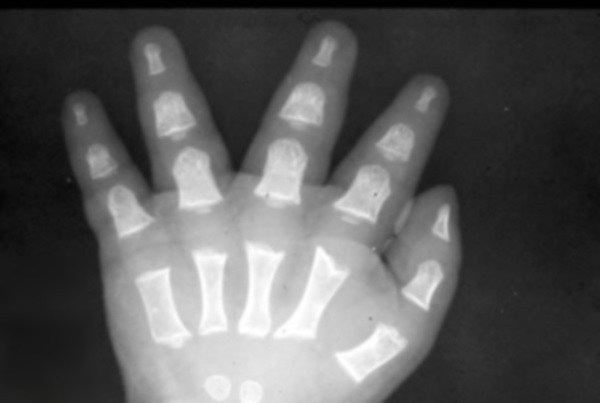

Braquidactilia: la pequeñez de los dedos es relativa a la longitud de otros huesos largos y otras partes del cuerpo. Las manos también son anchas, cortas y con formato de tridente.

| Créditos: Rixir.co.pk |

Además de las rizomelia, las radiografías esqueléticas muestran irregularidades metafisarias generalizadas, estrechamiento de la distancia interpedicular de las vértebras lumbares inferiores y una pelvis anormal con crestas ilíacas cuadradas pequeñas y muesca sacro-isquiática estrecha. Las mujeres afectadas deben dar a luz por cesárea debido al tamaño pequeño de la pelvis.